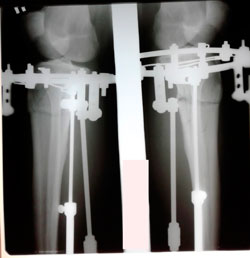

на фиксации

image-31-10-20-02-13-1.jpg

image-31-10-20-02-13.jpg